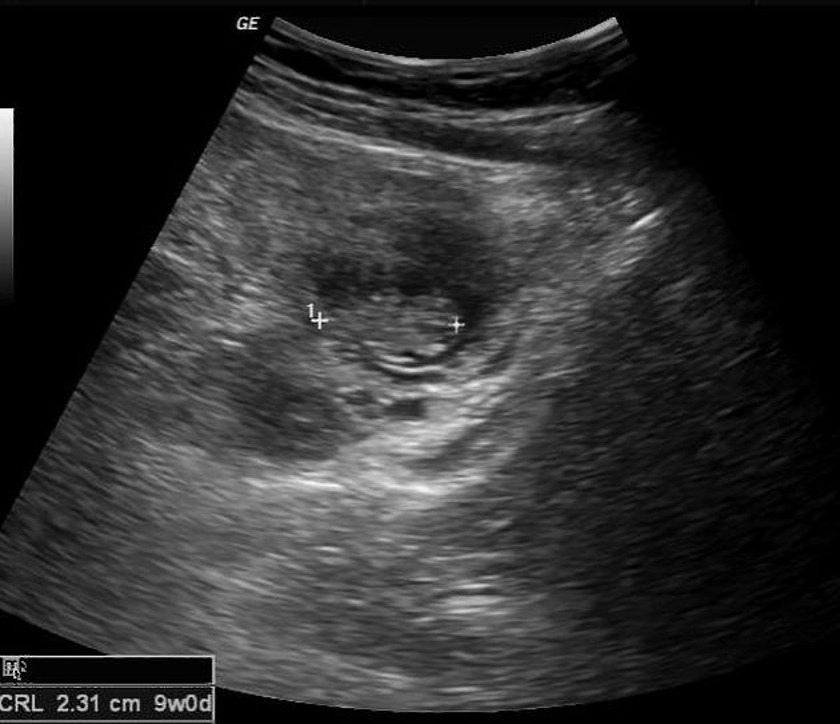

Case courtesy of Frank Gaillard, Radiopaedia.org, rID: 35931

Case courtesy of Maulik S Patel, Radiopaedia.org, rID: 46956